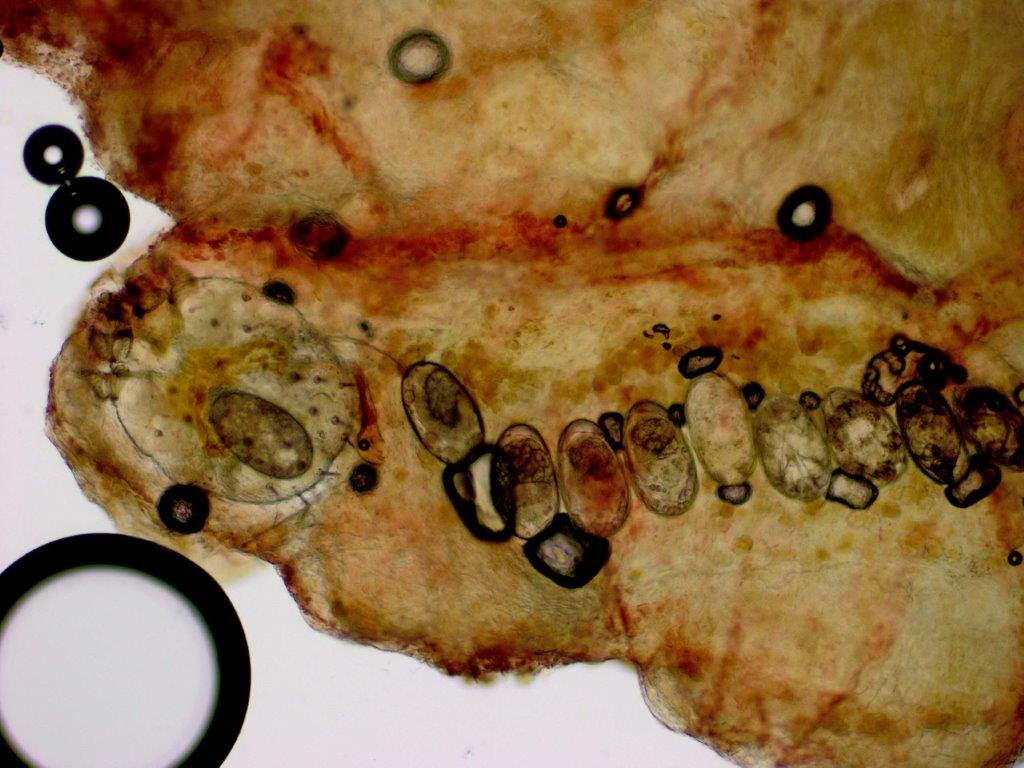

Schurftmijt onder de microscoop (KOH-preparaat) |

Diagnostiek:Preparaat maken: zoek een

papeltje of gangetje op tussen de vingers of op een andere voorkeurslokalisatie.

Snij met een mesje de bovenste laag van de huid af. De mijt leeft in de hoornlaag,

maar om een goed en groot genoeg preparaat te krijgen is het beter om iets van

de epidermis mee te nemen. Breng het in KOH onder een dekglaasje. Zoeken naar

mijten, gangetjes en eieren. Een andere methode is de dermatoscopie, waarbij